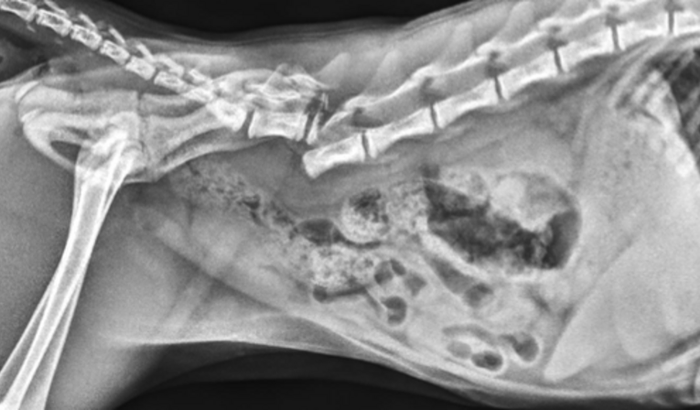

Oi, gente! No dia 25/04/2023, minha gata sofreu um acidente horrível ao cair do terceiro andar e acabou fraturando a coluna. Agora, ela precisa passar por uma cirurgia delicada e nós não temos condições financeiras para arcar com o custo da cirurgia. Por isso peço a ajuda de vocês.